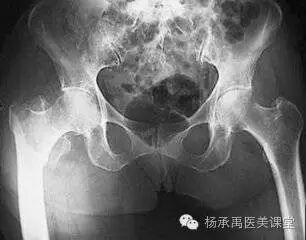

股骨颈骨折(转子间,股骨颈),股骨颈是松质骨丰富又是体重由躯干走向股骨干的负重骨骼,故最易发生骨折。表现为腹股沟中点附近压痛,纵轴叩痛,股骨转子间骨折在大转子处压痛,病变下肢是内收或外旋畸形不能钻立和行走,股骨颈骨折90%发生在50岁以上,80%为女性,70岁以上发病率急剧增加,其发病率与年龄、骨质疏松的程度成正相关。

定性诊断:常根据骨皮质厚度、骨小梁粗细数量、骨髓腔横径与骨皮质厚度比及骨髓腔与周围软组织之间的密度差来判断。但X线估计骨密度的误差可达30~50%,一般认为骨量丢失达30%X线检查始能反映骨质疏松表现,其准确性受到许多因素的影响,故较少应用。但X线摄片可以作为排除其它疾病的一种方法,决定有无骨质疏松引起的骨折及骨折的类型程度等。

定量诊断:双能X线评定被认为是目前骨质疏松症诊断的金标准,其精确度较高,重复性好,它是以双能X线骨密度吸收仪(DEXA)在前后位测得的腰椎及髓部骨密度值为依据的。但腰椎前后位测量时,往往包括了椎体附件及增生的小关节或钙化的韧带,使测量的骨量高于实际椎体骨量,如用侧位测量法可以减小上述误差。依照1995年WHO规定的骨质疏松症诊断标准。用同性别的骨量峰值,减去所测得的骨量值(BMD)来衡量: